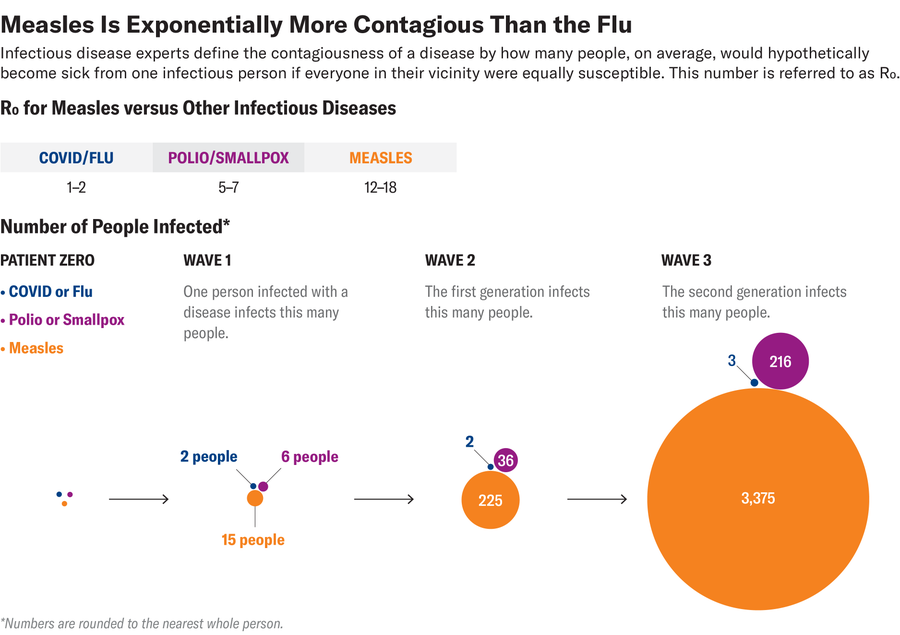

These side effects are of particular concern because the measles virus is highly contagious—an order of magnitude more than seasonal influenza. With measles, viral particles emitted by coughing or sneezing can linger in a room for hours after the infected person has left. One infected person infects 15 more people on average.